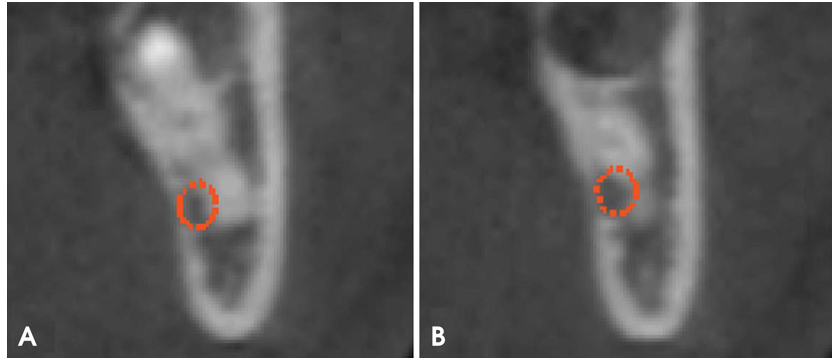

在微型螺钉安装后3周,智齿明显突出(图2),CBCT(图3)证实了这一点。此时,下8被手术取出。牙根没有断裂,下8很容易从牙槽窝中取出。手术期间,没有过度出血或疼痛。临床上未观察到下牙槽神经损伤或暴露。在取出和清洁下8后,通过检查下8观察到与下颌管接触的根部弯曲(图4)。

图4 拔除的下第三磨牙的近中侧(A)(箭头)和舌侧(B)视图显示了牙根弯曲 ,在用微型螺钉进行正畸牵引之前,牙根弯曲与下颌管接触。